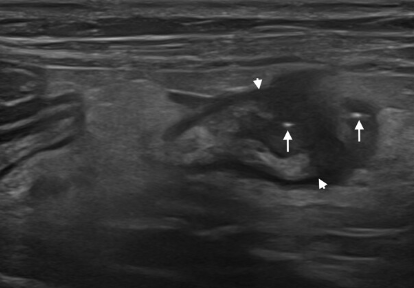

화살표로 표현된 것처럼 장 분절 내부뿐 아니라 복막에서도 공기방울 즉, 기복을 보고 천공가능성을 확인할 수 있다.